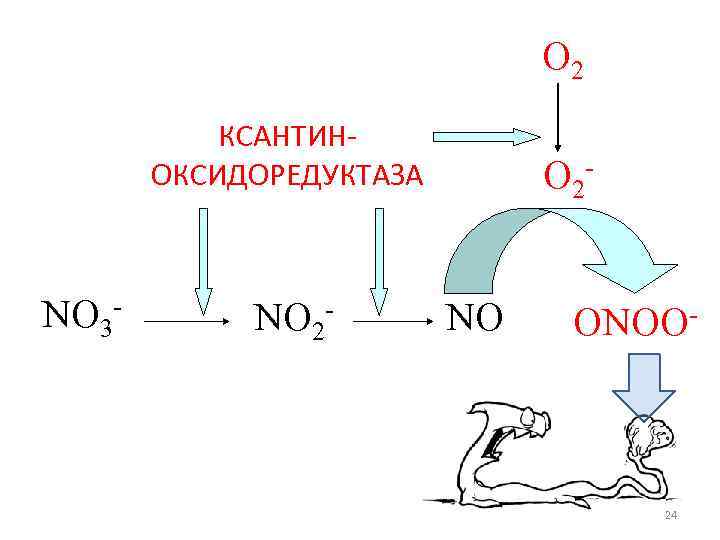

Ключевой эндогенный свободнорадикальный продукт, разрушающий гельминтов в организме млекопитающих, - пероксинитрит -!!! ONOO 13

ONOO-!!! NO ONOO 14

O 2 КСАНТИНОКСИДОРЕДУКТАЗА NO 3 - NO 2 - O 2 NO ONOO- 24